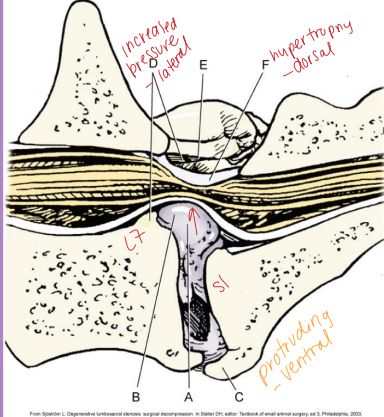

Lumbosacral Disease (Cauda Equina Syndrome)

Et: L7-S1/3 → spinal cord stops @ L5-6

Degenerative: disc protrusion, lig hypertrophy, facet hypertrophy, spondylosis, instability

Congenital: stenosis, malformation, transitional vertebrae, end plate OC

Sig: Lg, middle-aged, working dogs, GSD

Cs: reluctance to jump, stiff gait, low tail, incontinence, back pain, weakness(non-weight bearing), LMN signs(L4-3)

Patellar “pseudohyperreflexia” – exaggerated reflex

Sciatic affected, patellar reflex spared

Dt: rads (spondylosis, narrowed disc), CT, MRI(best)

Tx: NSAID, gabapentin, 4-6w rest, epidural steroids (MPA protocol: wk 0, 2, 6)

SX: laminectomy + discectomy = reoccurrence 1-2y esp. w/ lateral compression